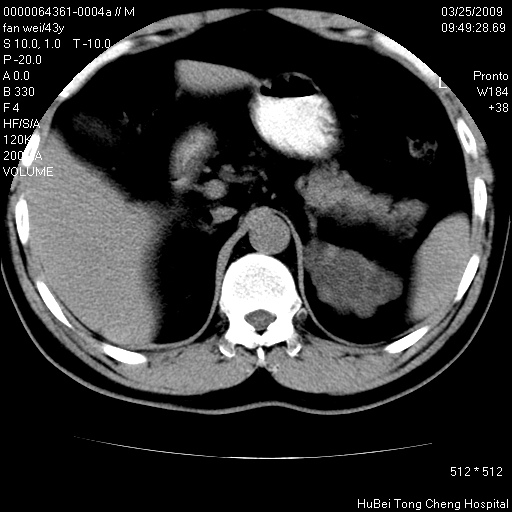

患者 男,43岁。左侧腰部不适两天。平素健康。无家族遗传病史。

双肾ct轴位平扫+增强扫描(层厚10mm,螺距1.0,重建间隔10mm),图像如下:

多囊肾的影像诊断标准:有阳性家族史,年龄<30岁,单侧或双侧肾脏有两个肾囊肿;30~59岁,两侧肾脏各有两个肾囊肿;60岁以上,每侧肾脏有4个囊肿。敏感性和特异性达86%和80%。

此病例影像诊断符合,要结合家族史,腰痛、血尿、尿路感染史,有无高血压等综合判断,如无相应的临床症状,本身病变也无意义了(个人观点)

囊肿数得清,肾功能正常,考虑多发肾囊肿.另外,右肾后极突向肾周间隙的那个病灶是不是错构瘤,请楼主调窗看看.